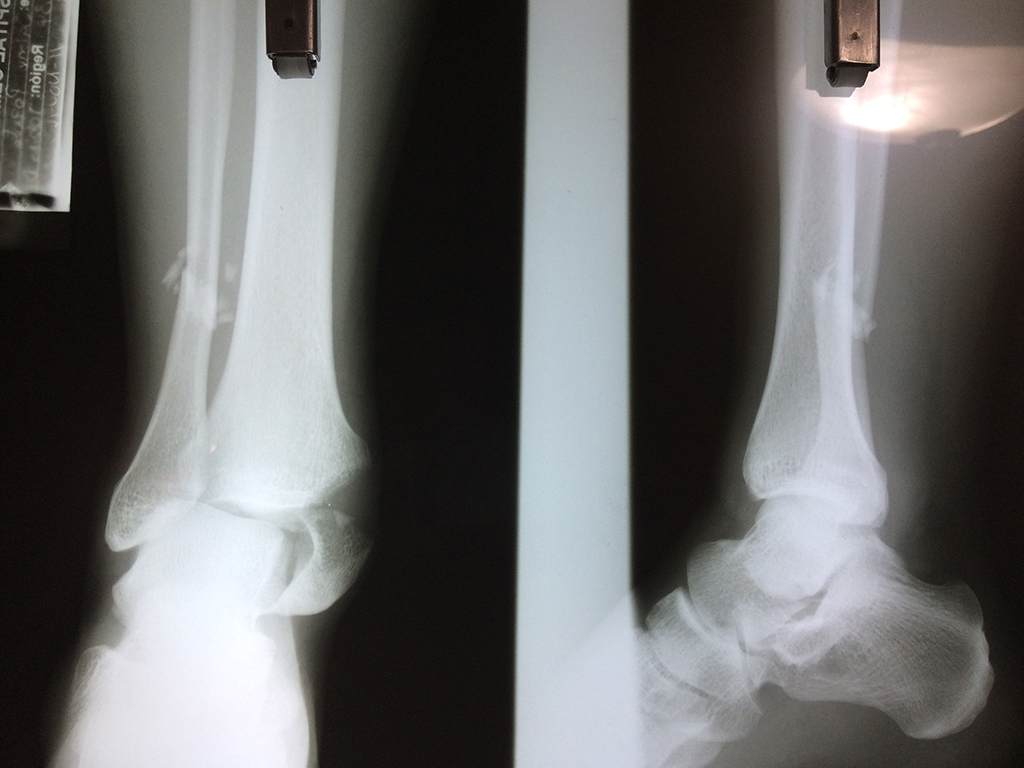

Algunas fracturas de tobillo pueden requerir cirugía si:

- Los extremos de los huesos están desalineados entre sí (desplazados).

- La fractura se extiende hasta la articulación del tobillo (fractura intra-articular).

- Los tendones o ligamentos (tejidos que sujetan los músculos y los huesos entre sí) están rotos.

- El médico cree que sus huesos probablemente no sanen apropiadamente sin cirugía.

- El médico considera que la cirugía puede permitirle una recuperación más rápida y confiable.